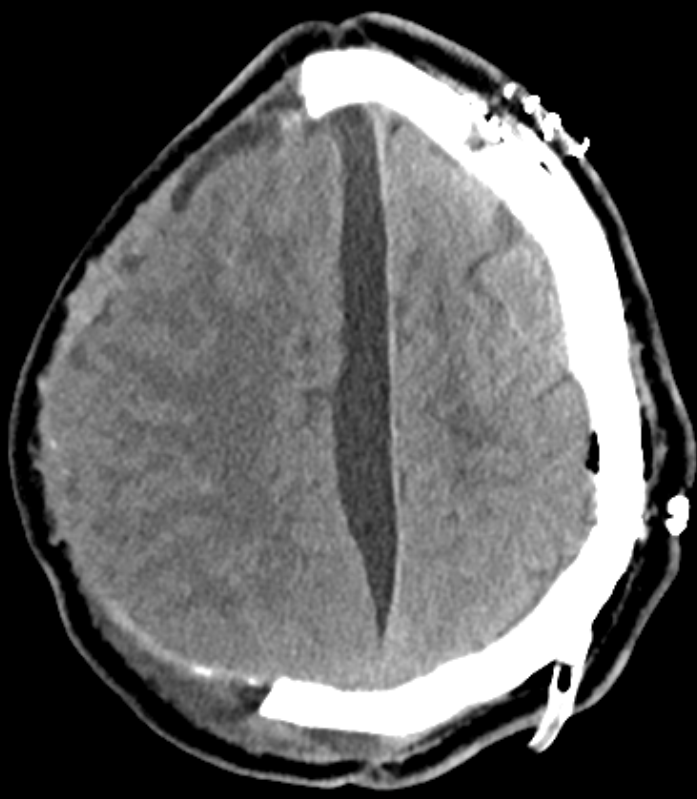

In der CT- oder MRT Bildgebung, äußern sich Hygrome oft als flüssigkeitsgefüllte Räume, die ähnlich wie chronische Subduralhämatome aussehen.

CT

In der CT Bildgebung sind Hygrome typischerweise als hypodense Bereiche sichtbar